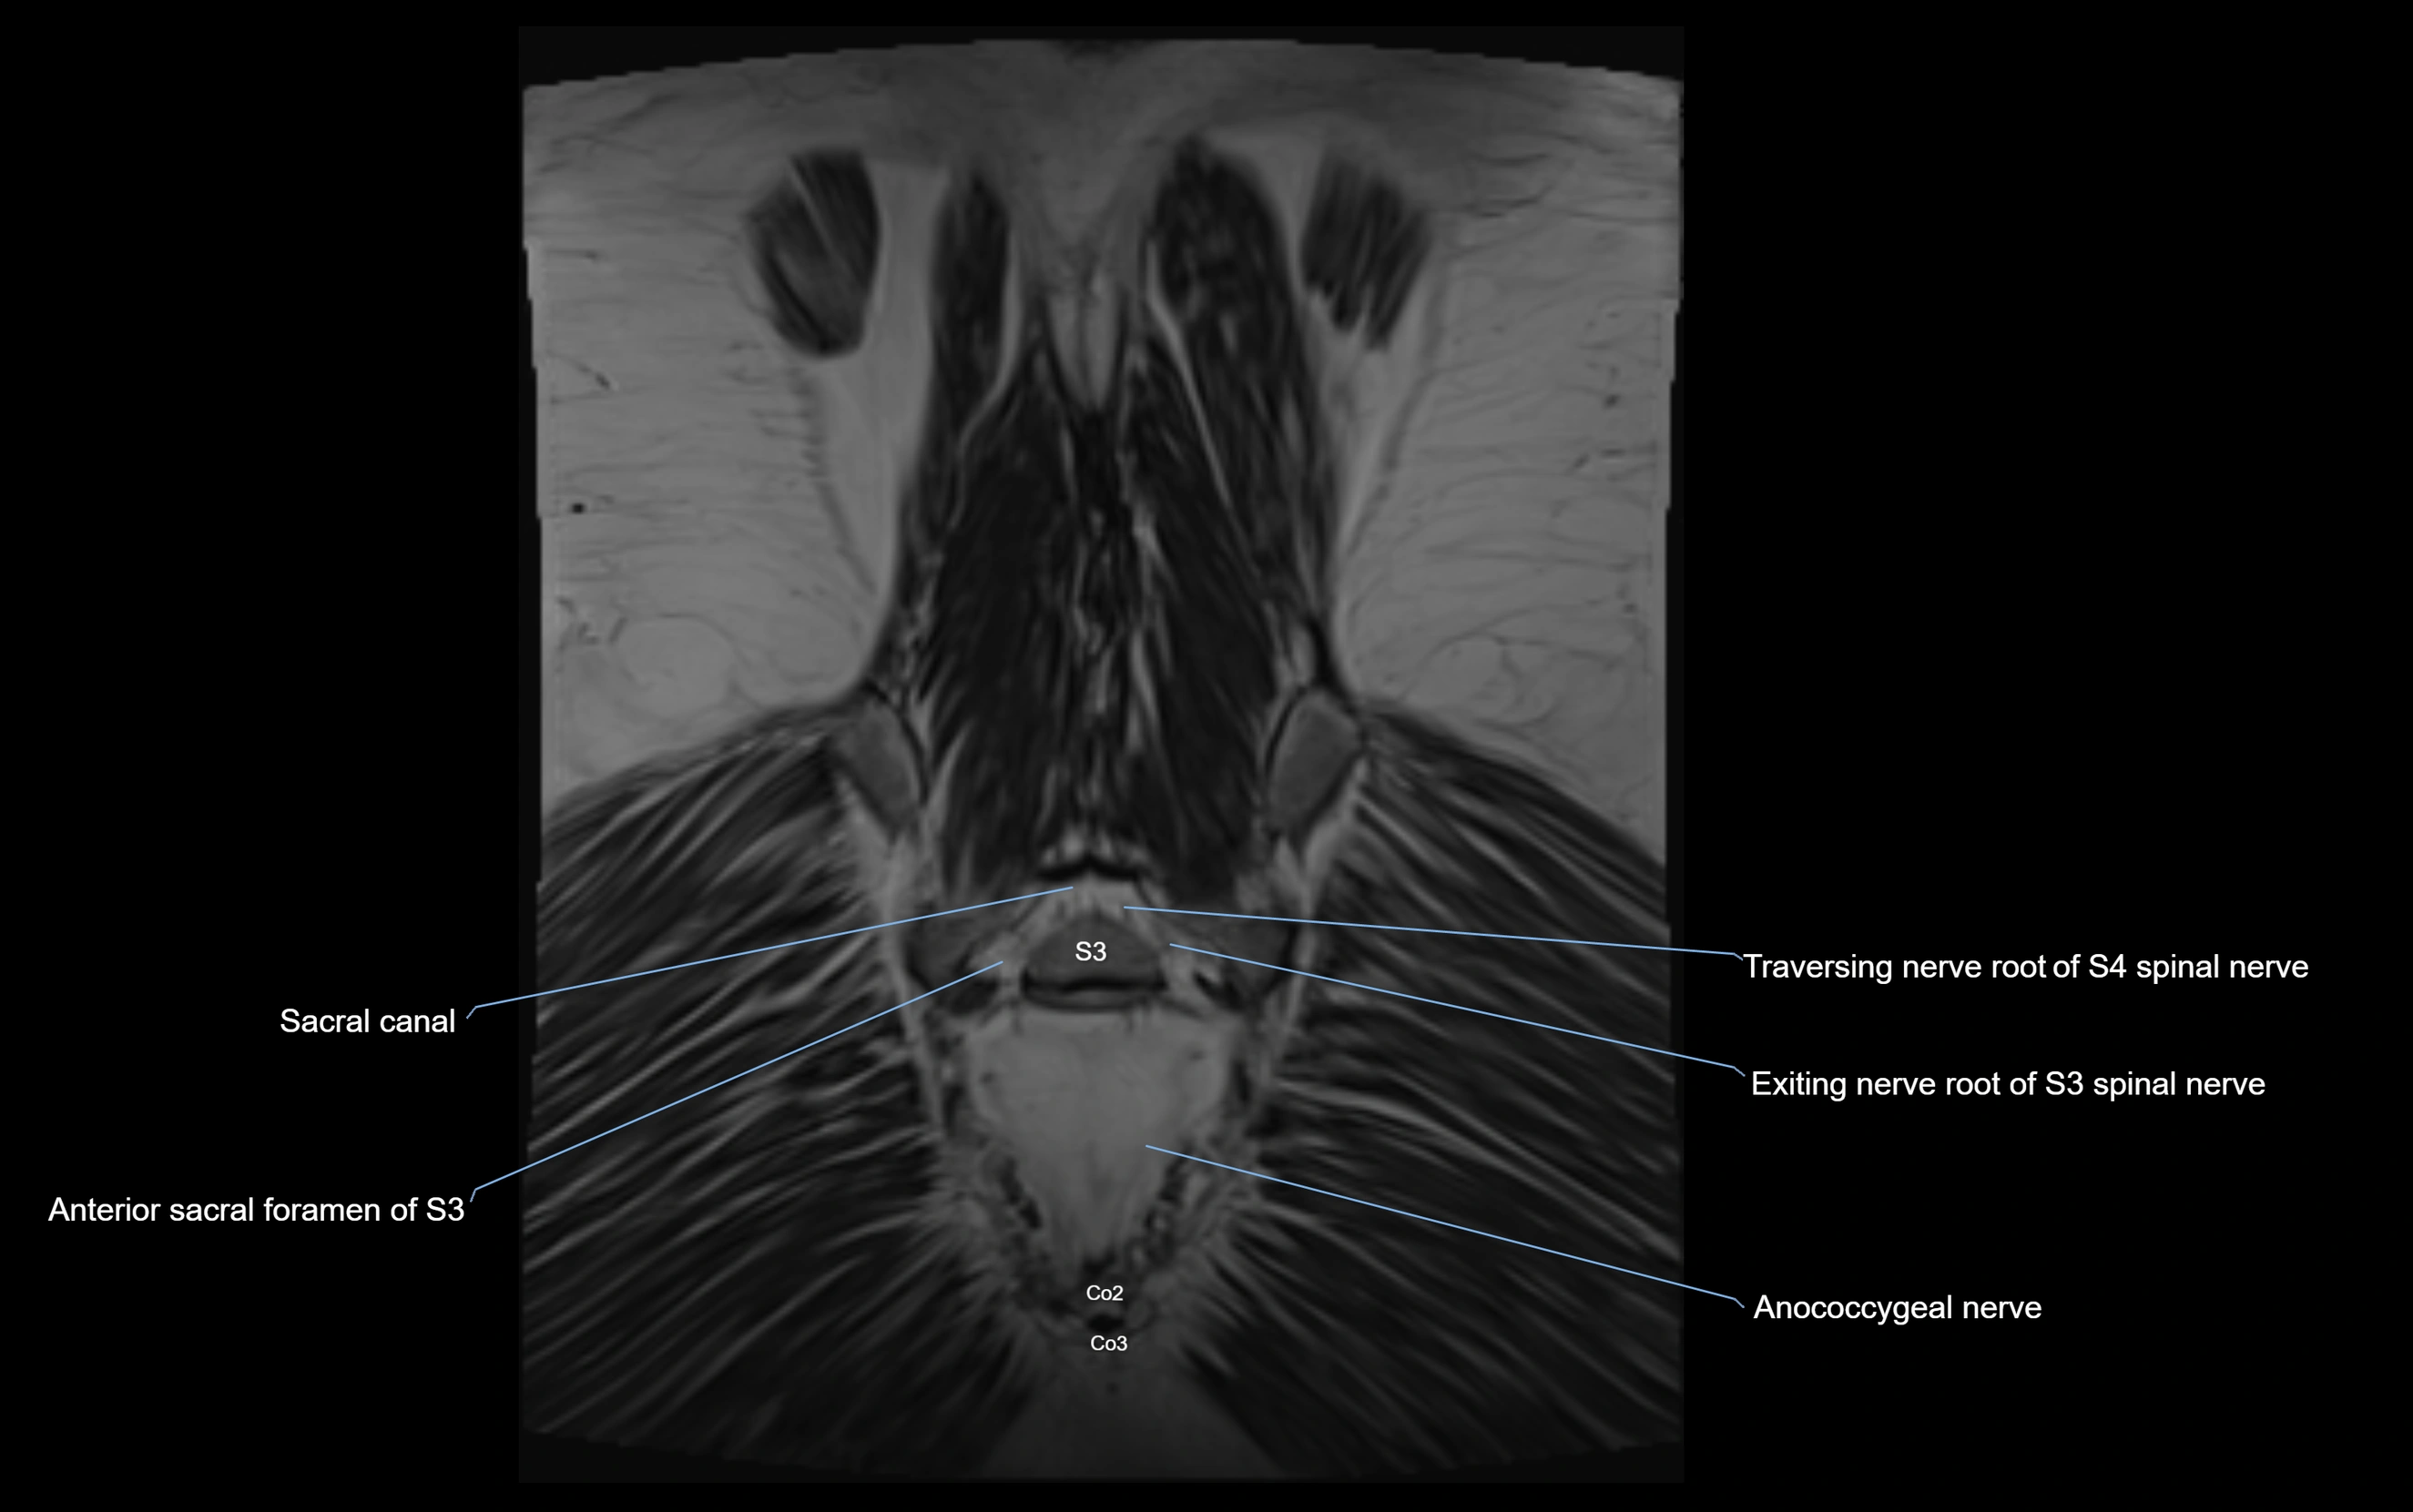

Anococcygeal nerve

The anococcygeal nerve is a small sensory nerve derived from the coccygeal plexus, which itself is formed by the ventral rami of S4, S5, and the coccygeal nerve (Co1). Although tiny, this nerve plays an important role in supplying the skin of the coccyx and the area between the anus and coccyx. It passes through the sacrotuberous ligament and runs in the midline behind the coccyx.

Despite its small size, the anococcygeal nerve is clinically important because of its involvement in coccygodynia (coccyx pain) and perineal pain syndromes.

MRI image

image